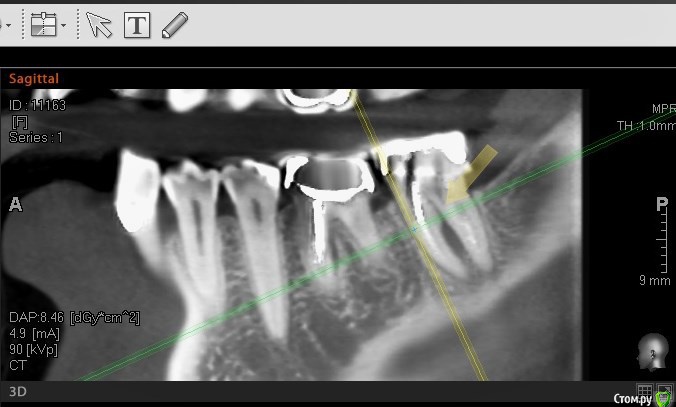

колесников Опубликовано 15 августа, 2016 Поделиться Опубликовано 15 августа, 2016 Здравствуйте, трещину седьмого зуба не увидел на кт, возможно в полости рта видно. На КТ он выглядит вполне нормально для попытки спасения.С шестым вот большой вопрос в сохранении, возможно нарушена целостность корня. Верхний шестой тоже обязательно лечить, вокруг корней тоже воспаление. Итого: то что видно на КТ. на трех зубах очаги воспаления. Трещин не видно ( их и не будет видно) Все три зуба можно попытаться вылечить, шансы 50/50. По моему всё очевидно. 37 трещина по бифуркации,тотальная резорбция межкорневой перегородки и ограниченно -вестибулярной пластинки. 36 перфорация медиального корня в верхней трети с очаговой деструкцией в области межкорневой перегородки. Итого: 37 удаляется без вариантов. 36 удаление можно отсрочить на несколько месяцев ,но шансы на восстановление у него призрачны (перспективы перелечивания с закрытием перфорации в устье канала сомнительны,плюс остаётся нерешаемый очаг деструкции в перегородке) 2 Ссылка на комментарий

колесников Опубликовано 16 августа, 2016 Поделиться Опубликовано 16 августа, 2016 (изменено) Есть проблема и у верхней шестёрки. Деструкция на верхушке медиального щёчного корня. Это лечится. Есть карман пародонтальный между 26 и 27. Это лечится. Но есть и подозрение на кариес корня . Этот вопрос решится только после снятия коронки. Изменено 16 августа, 2016 пользователем колесников Ссылка на комментарий